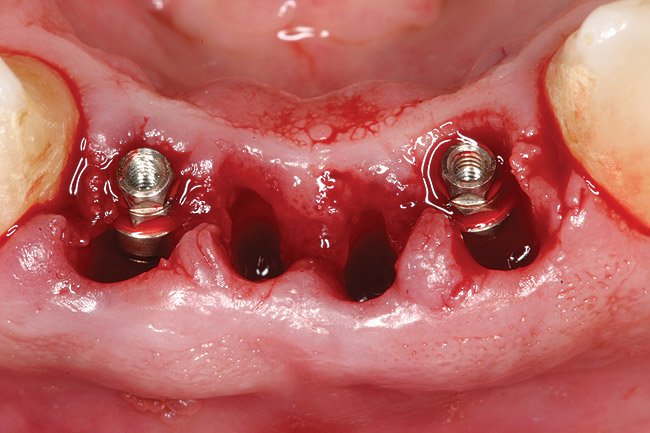

Figure 3a 3  Osteotomies prepared lingually.

Figure 3a

Figure 3  Placement of implants without flap elevation.

Figure 3

Preoperatively, 1 g of amoxicillin was administered. Using local anesthesia (lidocaine 1:100,000 epinephrine), extractions of teeth No. 23 to No. 26 were performed without raising a flap and with gentle luxation to preserve the remaining facial osseous plate. The sockets were curetted prior to implant placement. A vacuum-formed surgical guide, fabricated based on a diagnostic wax-up of the desired tooth positions for the subsequent fixed prosthesis, was used during implant placement. Osteotomies were performed at sites No. 23 and No. 26 and positioned toward the lingual aspects of the sockets (Figure 3A and Figure 3B). Two tapered implants (OsseoTite™ 313, BIOMET 3i™, Palm Beach Gardens, FL) measuring 3.25 mm x 13 mm were placed. Conical prosthetic abutments (3-mm height) were used to facilitate joining the two implants in a screw-retained fixed partial denture (Figure 4). A laboratory-processed acrylic-resin provisional restoration was altered to allow connection to the temporary cylinders. The provisional was placed into the vacuum-formed surgical guide that was now used to maintain the provisional in the correct 3-dimensional position (Figure 5) while being attached to the temporary cylinders with acrylic resin intraorally. Once a sufficient amount of acrylic resin was placed to secure the cylinders to the provisional, it was removed from the mouth and its contours were completed at the laboratory bench (Figure 6A). The two central incisor sockets were grafted with small-particle allograft material (Puros® Allograft, Zimmer Dental, Carlsbad, CA) to maintain gingival architecture beneath two ovate pontics (Figure 6B). The provisional restoration was inserted and the screws tightened to 20 Nt-cm of torque.